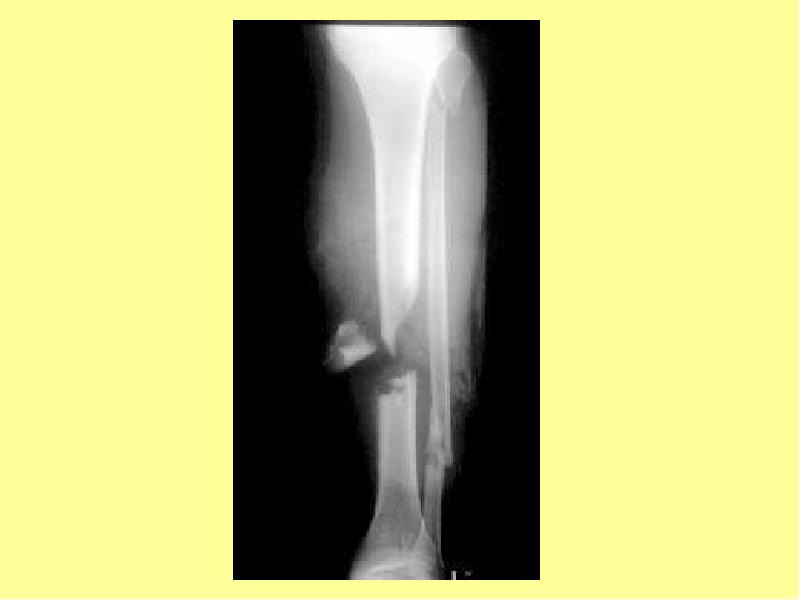

- 3. Виды травматических повреждений Ушиб Повреждение связок Повреждение сухожилий Травматические вывихи Переломы